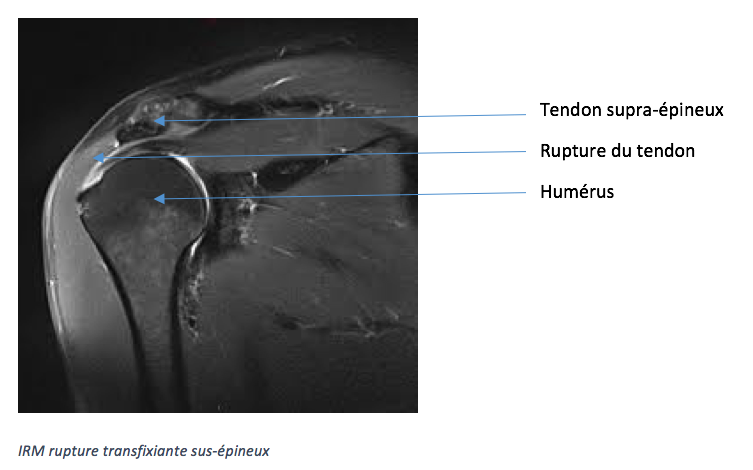

L’arthroscanner ou l’IRM est utile en pré-opératoire. Elle confirme le diagnostic de rupture et permet de préciser le nombre de tendons lésés, l’importance de la déchirure, le recul du tendon ainsi que la trophicité des muscles.